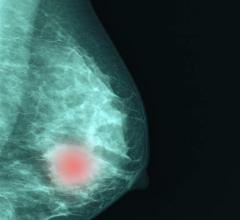

AI is also helping simplify complex tasks and help reduce the reading time on involved exams. One example of this is in 3-D breast tomosythesis with hundreds of images, which is rapidly replacing 2-D mammography, which only produces 4 images. Another example is automated image reconstruction algorithms to significantly reduce manual work. AI also is now being integrated directly into several vendors' imaging systems to speed workflow and improve image quality.

How AI is Helping the Fight Against Breast Cancer

Artificial Intelligence Improves Accuracy of Breast Ultrasound Diagnoses